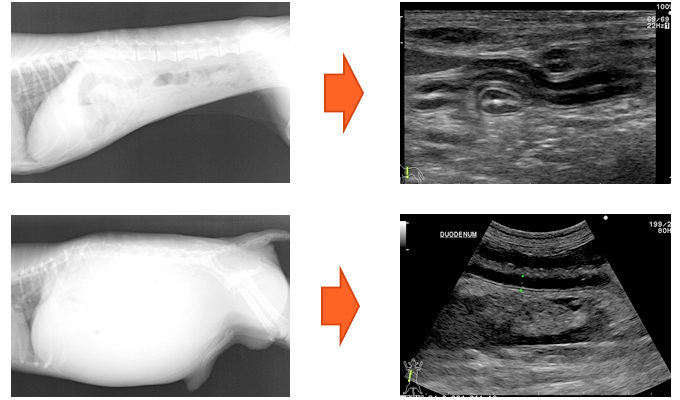

小動物獣医師のための迅速超音波検査法 裁断済】小動物獣医師のための迅速超音波検査法 - メルカリ

ほぼ新品です。定価17000円